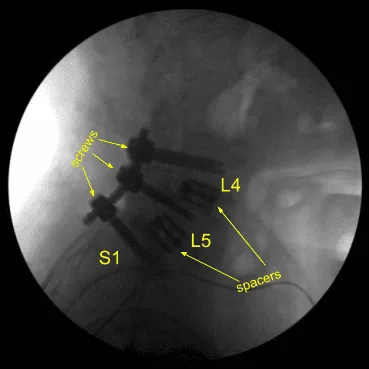

Expandable titanium interbody spacers, 15-degree lordotic at L5-S1 and 10-degree lordotic at L4-5, were placed under fluoroscopic guidance and expanded to proper fit. There was partial subsidence of the interbody spacer at L5-S1 into the L5 body, but it was secured and tight fit and imaging showed midline positioning.

CT scan was then obtained (shown above) which showed correct positioning of all the hardware. Neuromonitoring signals were stable. The wound was irrigated copiously. Bilateral transverse processes were decorticated for posterolateral arthrodesis from L4 to S1.

Precut titanium rods were contoured with rod benders and placed across the screw tulips from L4 to S1and secured with locking caps which were all final tightened with a torque and anti torque device. Final AP and lateral x-rays showed correct and complete hardware implantation.